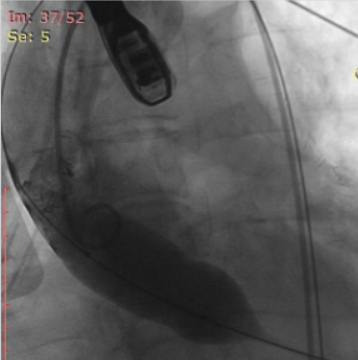

图3.术前24号球囊预扩